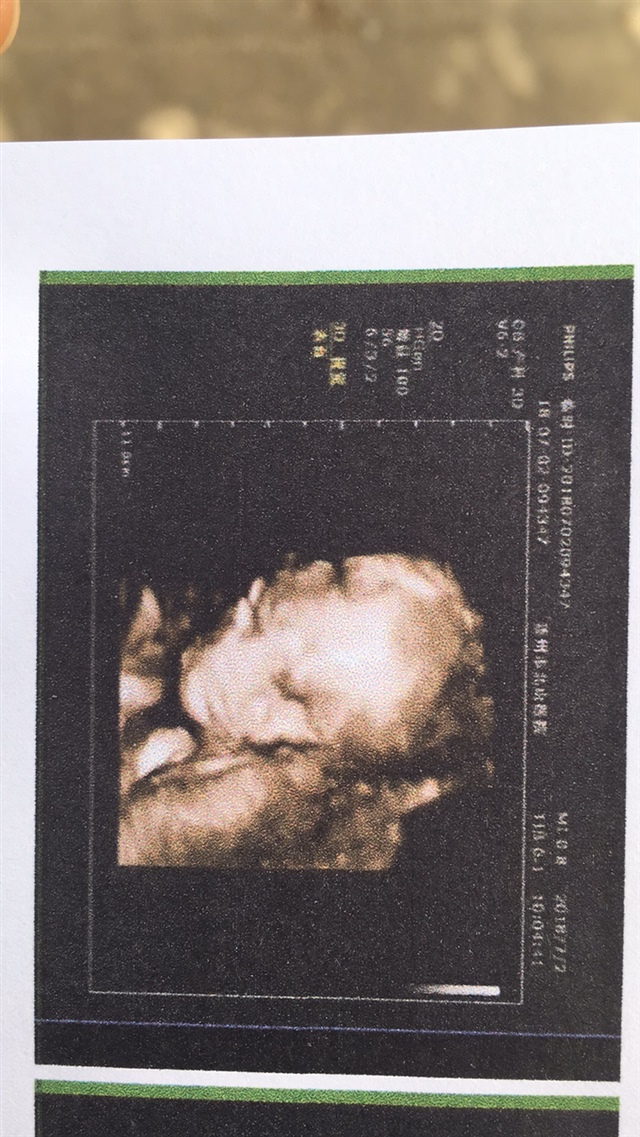

孕33周+5天